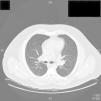

The chest x-ray revealed a parahilar mass consistent with the high-resolution computed tomography findings of multiple mediastinal, parahilar, and supraclavicular lymph nodes and multiple pulmonary nodules (Fig. 1). Given the possibility of a lymphoproliferative disease, mediastinoscopy was performed to take a lymph node biopsy. Histology showed chronic noncaseating granulomatous inflammation with a negative Ziehl-Neelsen stain and negative polymerase chain reaction test for Mycobacterium tuberculosis (Fig. 2).